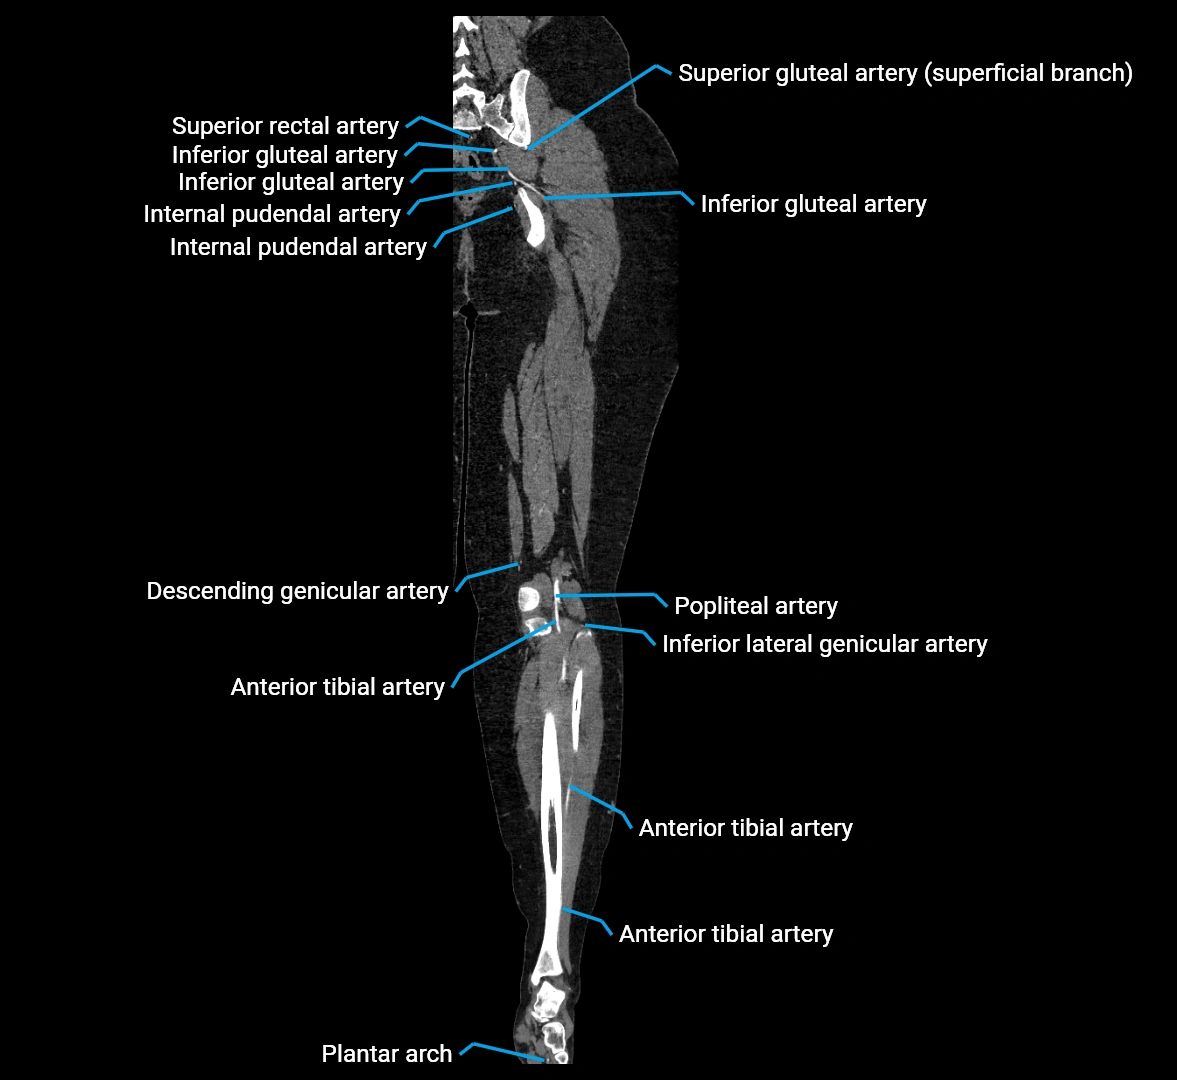

CT images

image

Contrast-enhanced CT (CTA):

• Gold standard for abdominal aortic imaging

• Provides excellent detail of lumen, wall, aneurysm, thrombus, and branch vessels

• Multiplanar and 3D reconstructions help in aneurysm measurement, stent graft planning, and dissection evaluation

• Detects acute rupture, traumatic injury, or occlusion with high sensitivity